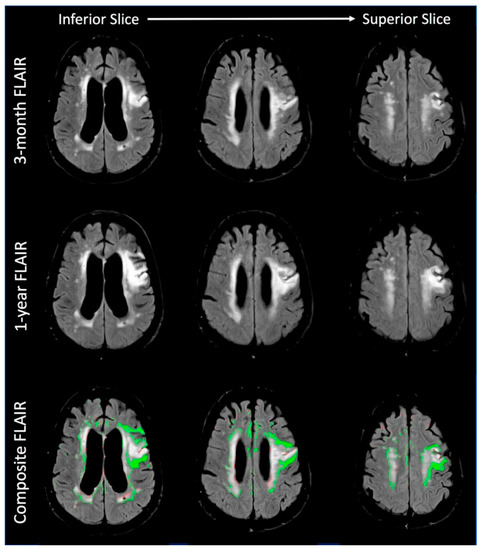

3.1.1. Imaging Findings